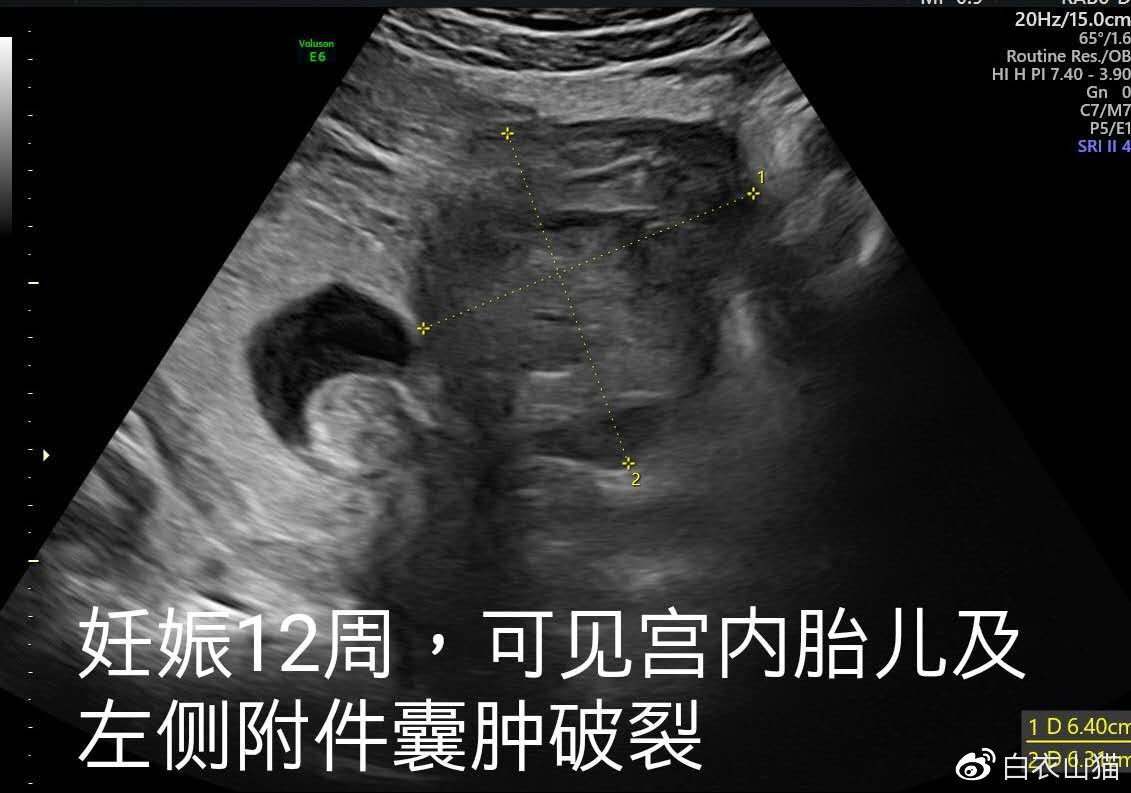

最后一次B超,发现左侧附件囊肿破裂。

小兰的腹痛慢慢缓解,昨天,她要求出院了。医生不放心,再次给她做了B超。这个时候,发现了小兰左侧的囊肿好像破了。

因此,产科请妇科张教授去会诊小兰的病情。小兰和家属的要求是,左侧附件的囊肿,能不能等到胎儿16周以后,再来做手术处理?因为到了那时候处理,胎儿保住的希望会更大一点,毕竟小兰已经33岁了,怀上一个孩子真不容易。